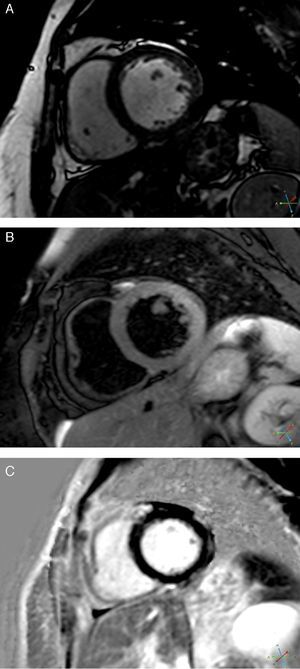

CMRI performed on the 7th day revealed a non-dilated and non-hypertrophied left ventricle, no longer showing wall motion abnormalities and with good global systolic function; there was a hyperintense myocardial signal in T2-weighted turbo spin-echo sequences located in the lateral wall and late gadolinium enhancement in the subepicardium of the same wall (Figure 5). The right ventricle presented no abnormalities.

These findings were compatible with acute myocarditis with involvement of the LV lateral wall, which was in agreement with the ECG changes, although the wall motion abnormalities at admission were compatible with TC.

The myocardial edema typical of TC,6 associated with evidence of irreversible injury (characteristic of acute myocarditis5) in the same location, was crucial to the diagnosis, since necrosis does not occur, or is negligible and residual, in TC. Subepicardial edema is also a typical finding of acute myocarditis on CMRI. There was a slight rise in biomarkers, as is usual in myocarditis. The underlying etiology could not be identified; viral serology was negative, but a viral etiology is frequently only established by polymerase chain reaction of biopsy specimens.